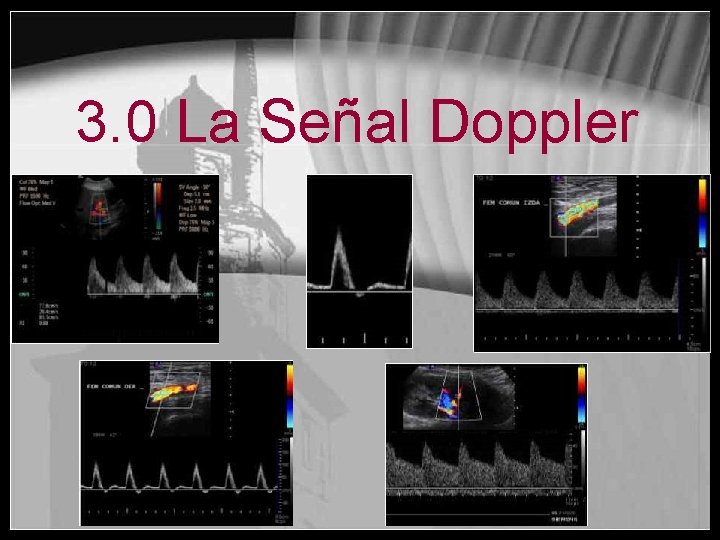

3. 0 La Señal Doppler